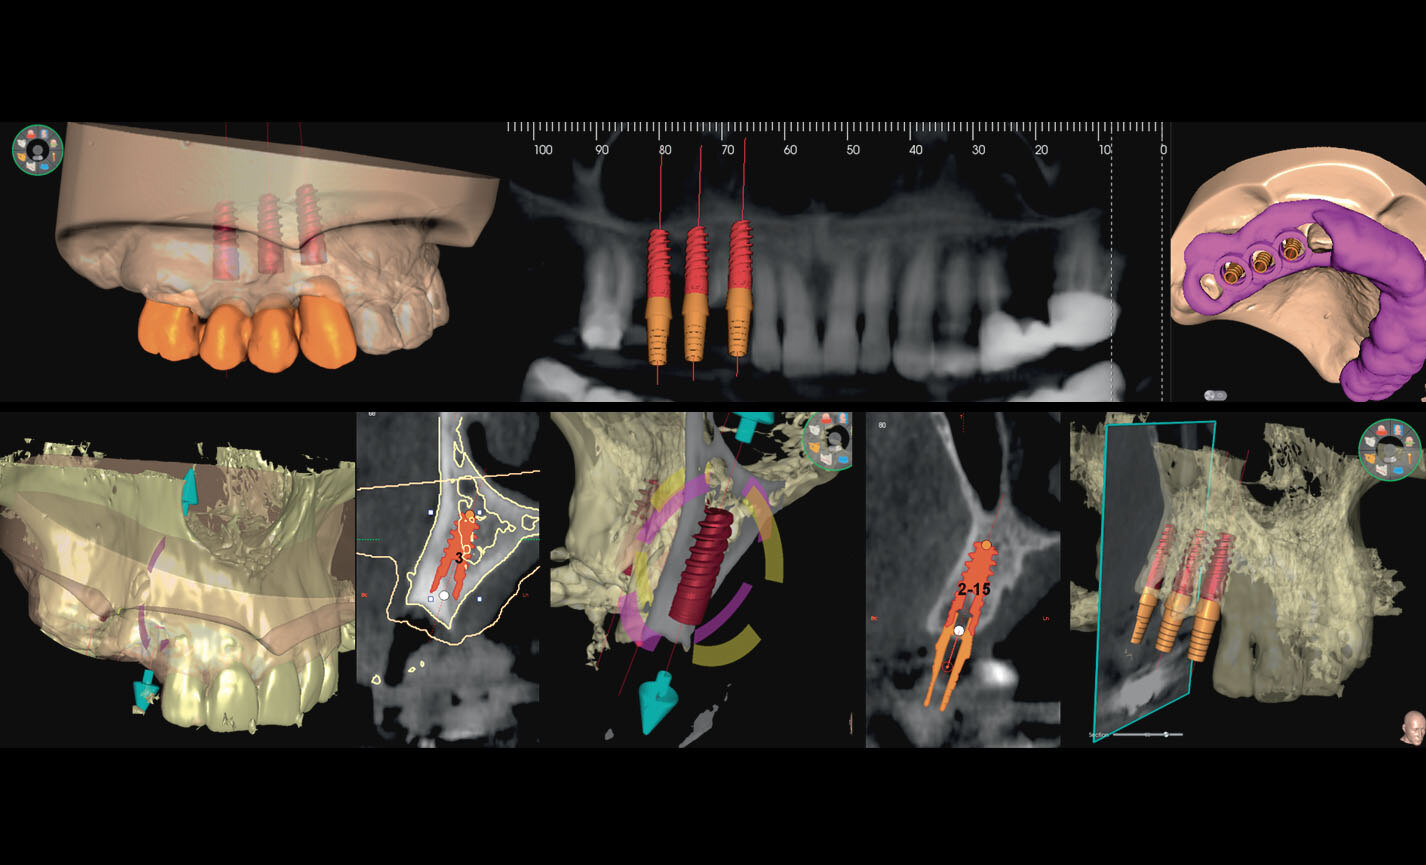

Planification implantaire avancée

Définissez la position de l’implant directement sur le modèle 3D, combinez-le avec les données STL provenant de scanners intra-oraux, et déterminez le projet prothétique définitif. Avec les instruments de planification implantaire avancée, vous pourrez opérer en toute sécurité, grâce aux informations précises sur la quantité d’os et la distance par rapport aux structures anatomiques avoisinantes, comme le canal mandibulaire, en définissant une distance minimale de sécurité.

Les volumes avec FOV 13 x 8 cm, ou 13 x 10 cm, représentent l’outil idéal pour la planification des implants zygomatiques. En effet, le diamètre de 13 cm est le seul qui permet d’inclure tout le zygoma dans le balayage, sans coupes.